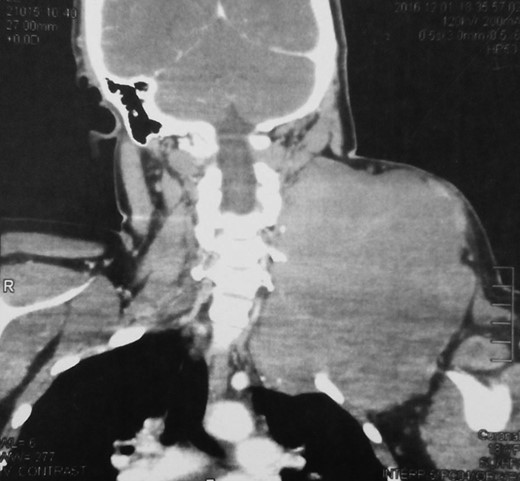

An 18-year-old primigravid Bedouin woman was admitted for resection of a 15 × 10 cm symptomatic, deforming solid mass fixed to her neck and left shoulder girdle (Fig. 1). Past medical history revealed a 1 × 1 cm dormant nodule, felt in her left sternomastoid, which grew explosively during her first pregnancy and stopped abruptly after delivery, with no history of major antecedent trauma. Physical examination showed limited abduction of her left shoulder, left arm weakness, forearm numbness, numbness of the three medial fingers and left wrist drop (Fig. 2). The tumor extended deeply medially into the neck causing right-sided deviation of the thyroid and trachea, with associated dysphagia to solids, but no change in voice. CT scanning revealed a mass attenuation inseparable from the paravertebral muscles extending into the left apical pleura (Fig. 3). MRI discerned that the tumor was not pressing on the brachial plexus, but rather infiltrating it. Pre-operative core-needle biopsy demonstrated a benign spindle cell neoplasm, consistent with a desmoid tumor. Immunohistochemical staining for estrogen receptors demonstrated a moderate positive reaction of most of the neoplastic cells. The patient underwent en bloc resection by dissection from the overlying skin, left internal jugular vein, left sternomastoid and trapezius muscles, left first rib, left apical pleura, and the left paravertebral muscles and cervical nerve roots. The tumor-encased brachial plexus was unsalvageable (Fig. 4). The incision closure included revision of the scar of a recently failed resection and insertion of a closed suction drain. Pathological evaluation of the excised tumor confirmed a 15 × 10 × 9 cm, non-encapsulated tumor with several enlarged, reactive-type cervical lymph nodes (Fig. 5). The patient’s postoperative course was notable for paralysis of the left upper limb, and a Chyle leak (trauma to the thoracic duct) through the drain, which stopped spontaneously 10 days after the operation (Fig. 6). A month after the resection, the patient underwent nerve transfer to salvage sensation to her left hand and the flexion–extension function around the elbow. Three intercostal nerves, along with the intercostobrachial nerve, were transposed and attached to the median nerve of the affected arm (Fig. 7).